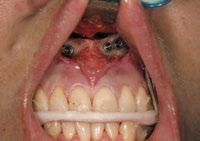

y lo que se pudo preservar del hueso malar. Se añadió una malla sinterizada infraorbitaria para dar volumen a la mejilla y se planificaron dos brazos de conexión que emergieran en las posiciones 24 y 26 de forma subgingival (Figuras 8 y 9). La superficie interna que apoyaba en el hueso era de titanio microrrugoso, y la superficie externa y conectores de titanio pulido y hexágono externo universal (Figuras 10 y 11). La cirugía se hizo bajo anestesia general en infiltración con anestesia local (4% articaína, 1:100.00 epinefrina), levantando el

colgajo cutáneo de la mejilla por vía intraoral, preservando el colgajo temporal para no comunicar con el remanente de la cavidad naso maxilar (Figura 12). Se emplearon 10 tornillos de osteosíntesis de 1,9 mm y la estabilidad primaria obtenida fue excelente (Figura 13)

4 meses después de la cirugía la encía estaba completamente cicatrizada y las conexiones de los implantes tipo hexágono externo universal quedaron a nivel yuxtamucoso. En este caso no se requirió el empleo de pilares transepiteliales y las impresiones fueron tomadas

directamente a cabeza de implante para realizar una prótesis dentoalveolar de cerámica de 3 piezas, que equilibraran la oclusión y dieran soporte al labio y la mejilla (Figuras 14-17)